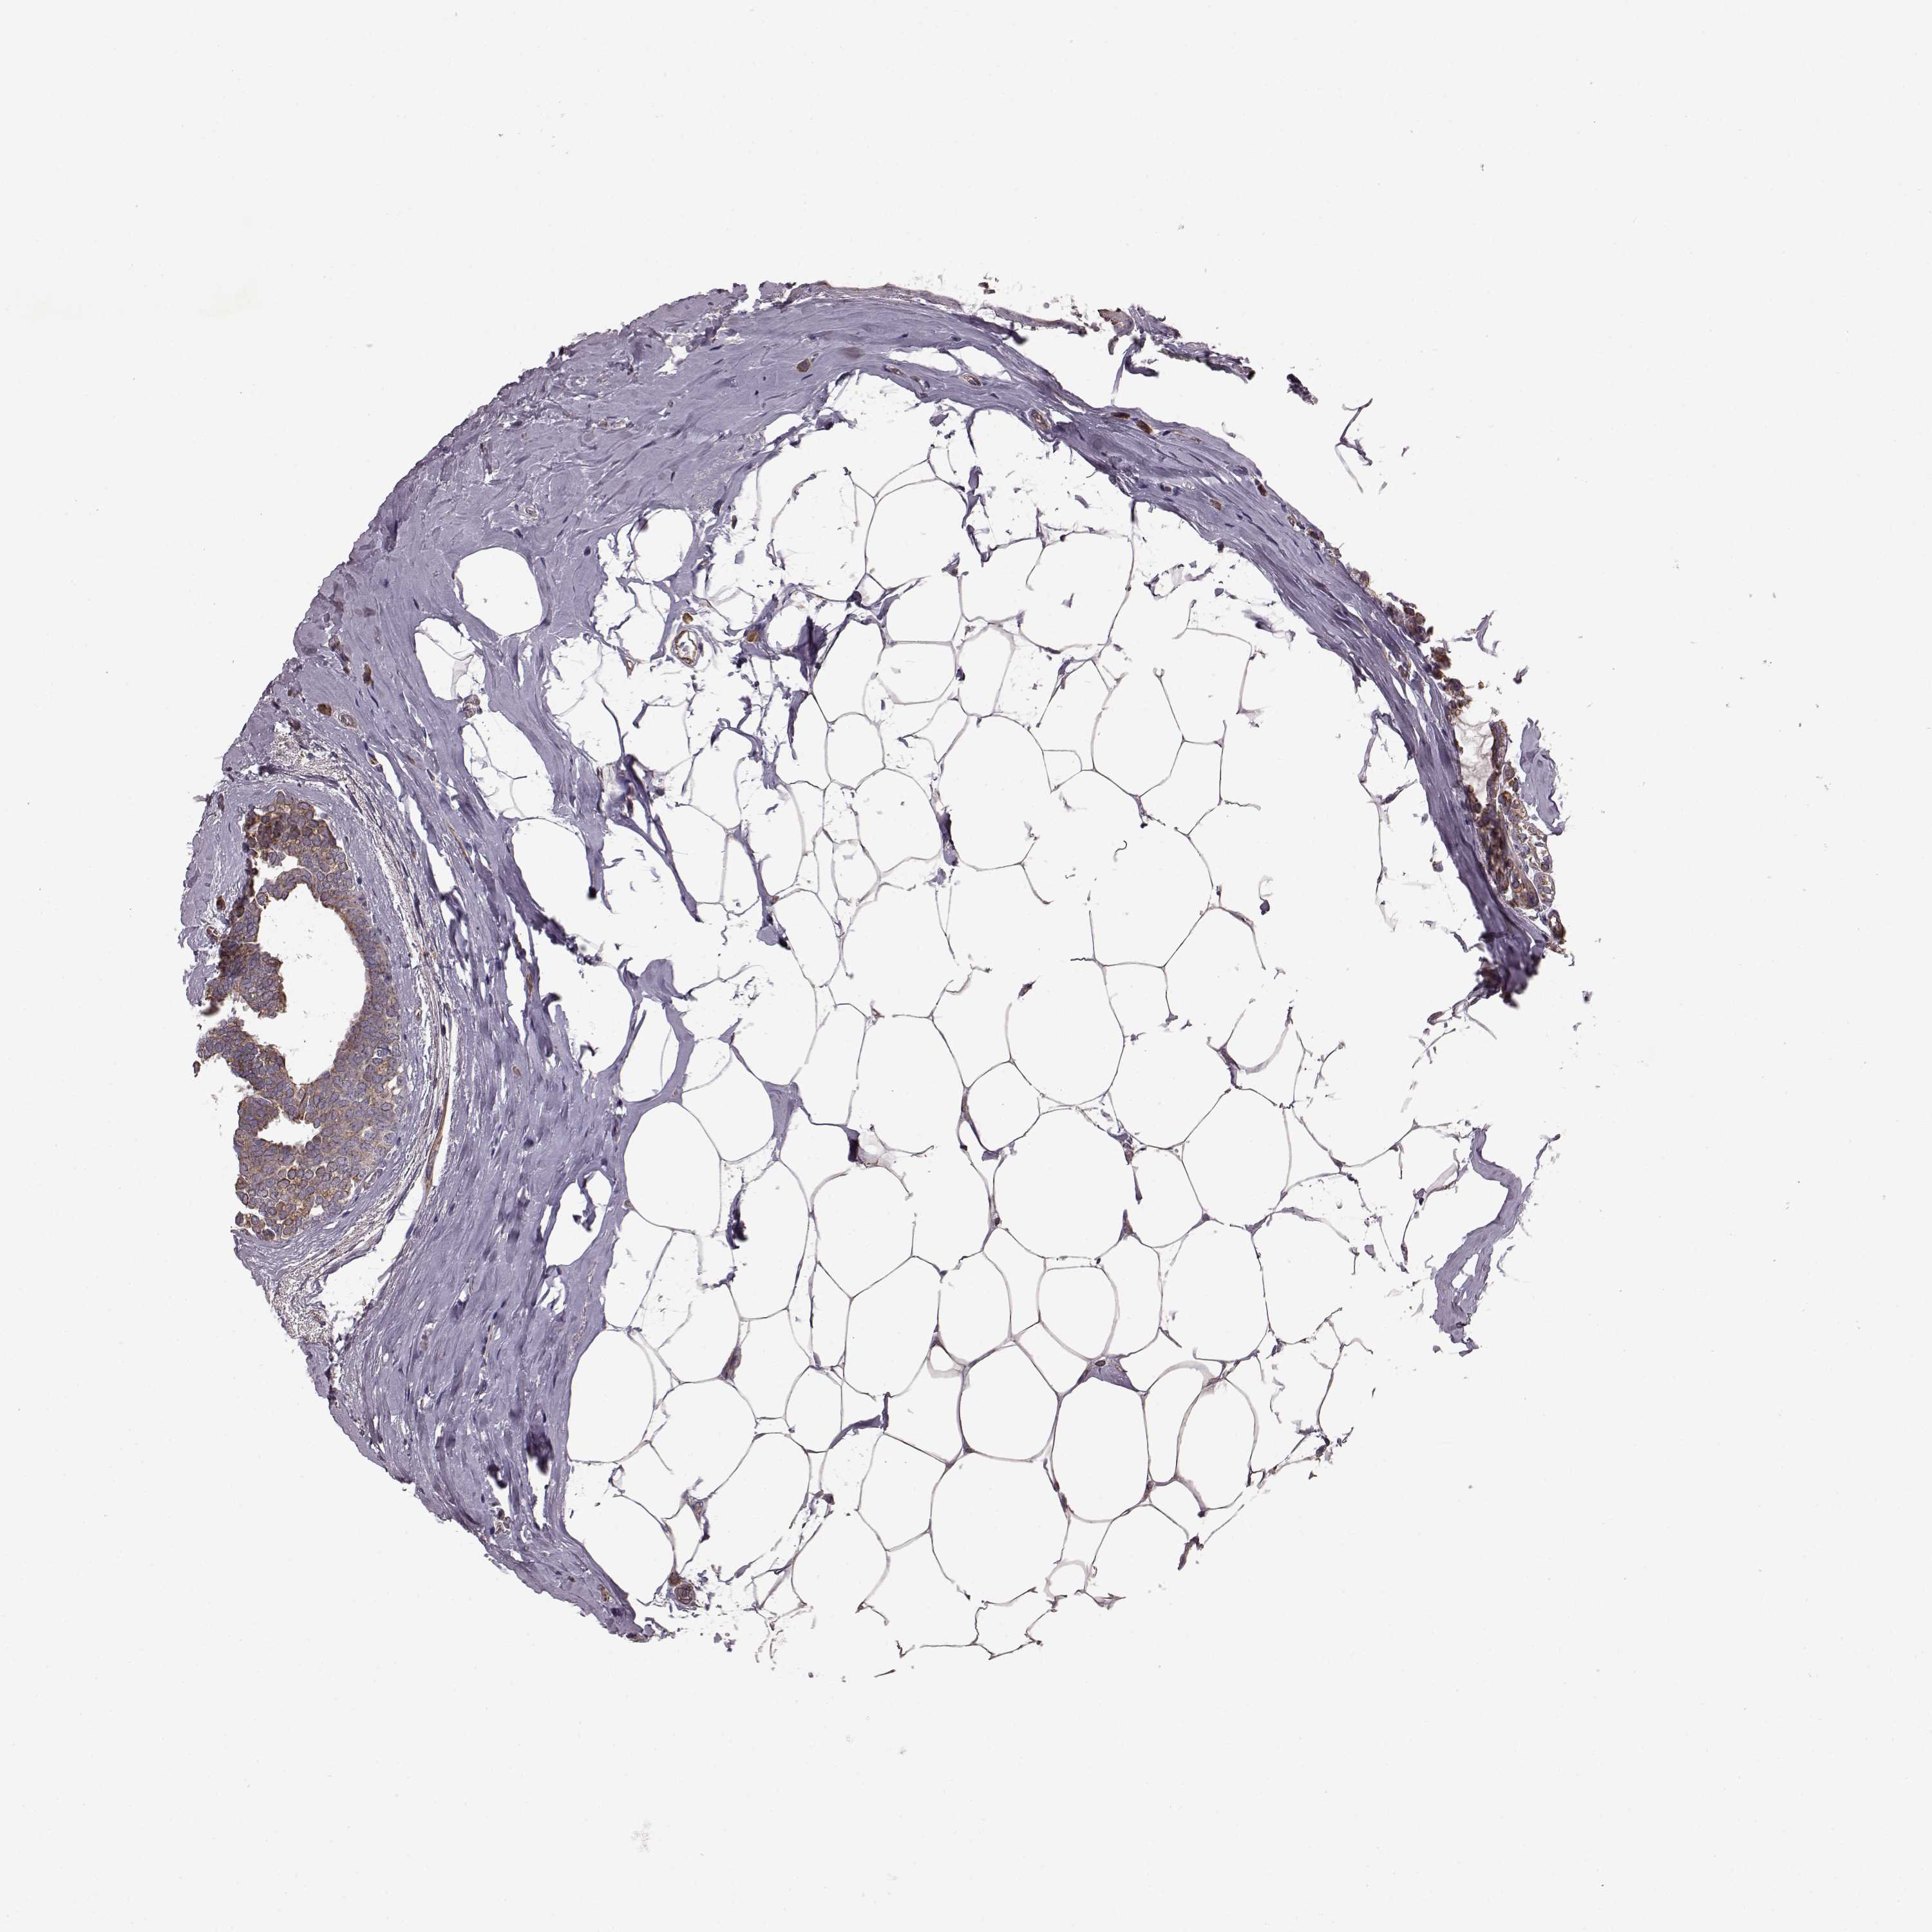

CANCER BREAST CANCER Show tissue menu

BRCA TCGA BRCA VALIDATION PROTEIN EXPRESSION